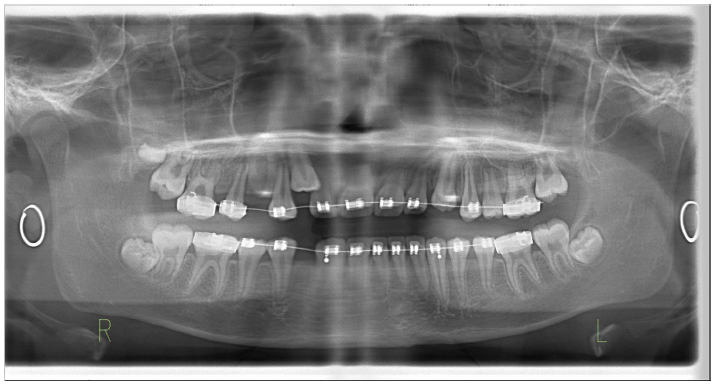

The treatment objectives were to expand the maxillary arch, coordinate arches, eliminate the posterior crossbite, and establish a Class I molar and canine relationship. Treatment was started by bonding metal 0.022-in slot pre-adjusted edgewise appliances with a rapid palatal expander (RPE) to correct the posterior crossbite. Instruction was given to the patient and parents to do one turn per day of the expansion screw for 14 days. The RPE was removed after a five-month retention phase. A pendulum appliance was then delivered to start the distalization process. After eight months, enough space was created for both maxillary canines, and a Class I molar relationship was achieved (Figs. 5 and 6). Detailing was performed using 0.017 x 0.025 titanium molybdenum alloy (TMA) archwire. Upon completion of treatment, maxillary and mandibular Hawley retainers were delivered, and the patient was instructed to wear the retainer for 24 hours per day (Figs. 7 and 8).